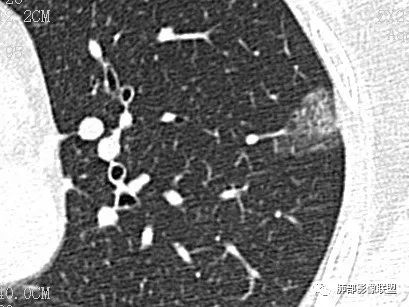

CASE 4

男 78 医学百科网 | YxBaike.Com

讨论 医学百科网 | YxBaike.Com

Clover: 医学百科网 | YxBaike.Com

错构瘤 医学百科网 | YxBaike.Com

实性结节,浅分叶,边缘光滑,挂果,考虑错构瘤

右肺上叶后段实性结节,边缘光滑清晰,密度离散度大,考虑错构瘤

边缘清,实性,浅分叶,血管贴边,良性结节,错构大过psp

边缘平直为主,彭隆感觉比较均匀,血管自然,支气管情况不明,倾向于良性。轻度凹陷,软骨型错构瘤第一位,炎性肉芽肿第二位。淋巴结未见,神经内分泌最后。 医学百科网 | YxBaike.Com

有黑晕,错构瘤

病理诊断

一句话小结:

肺部边缘光整结节影,孤立,有一定规模(大于1公分)且不在胸膜下,未见肺门纵隔淋巴结增大且没有原发肿瘤病史的,首先想到良性病灶。 医学百科网 | YxBaike.Com

病灶密度不均,或者说密度反差太大,即便未见典型的脂肪密度影或钙化亦应当首先先到错构瘤。 医学百科网 | YxBaike.Com

增强扫描有助于鉴别硬化性肺细胞瘤。 医学百科网 | YxBaike.Com